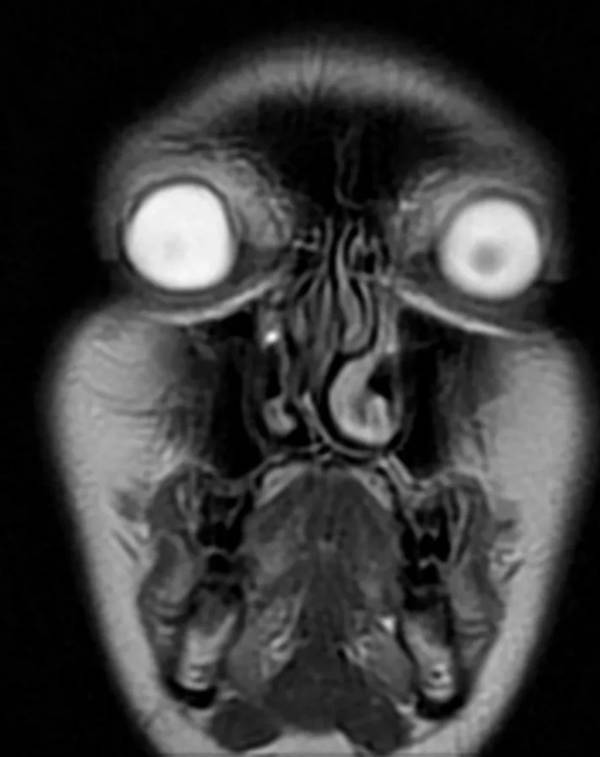

"Even the most beautiful woman looks terrifying under a scan!"